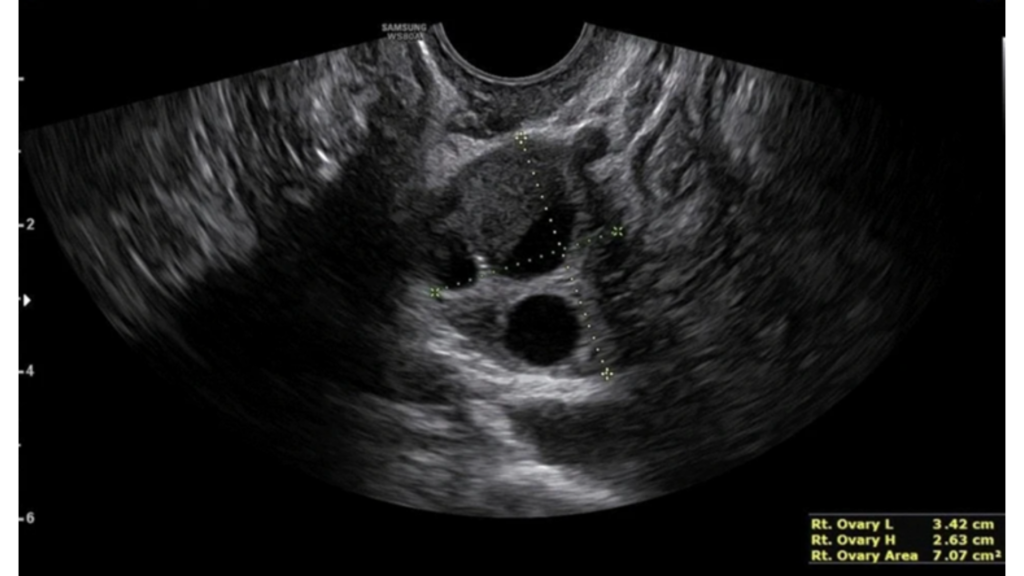

Estudio de Endometrosis

Se trata de un estudio simple, ambulatorio, sin radiación y de gran utilidad clínica, que permite una evaluación más completa que la ecografía ginecológica convencional cuando existe sospecha de endometriosis, especialmente en sus formas profundas.